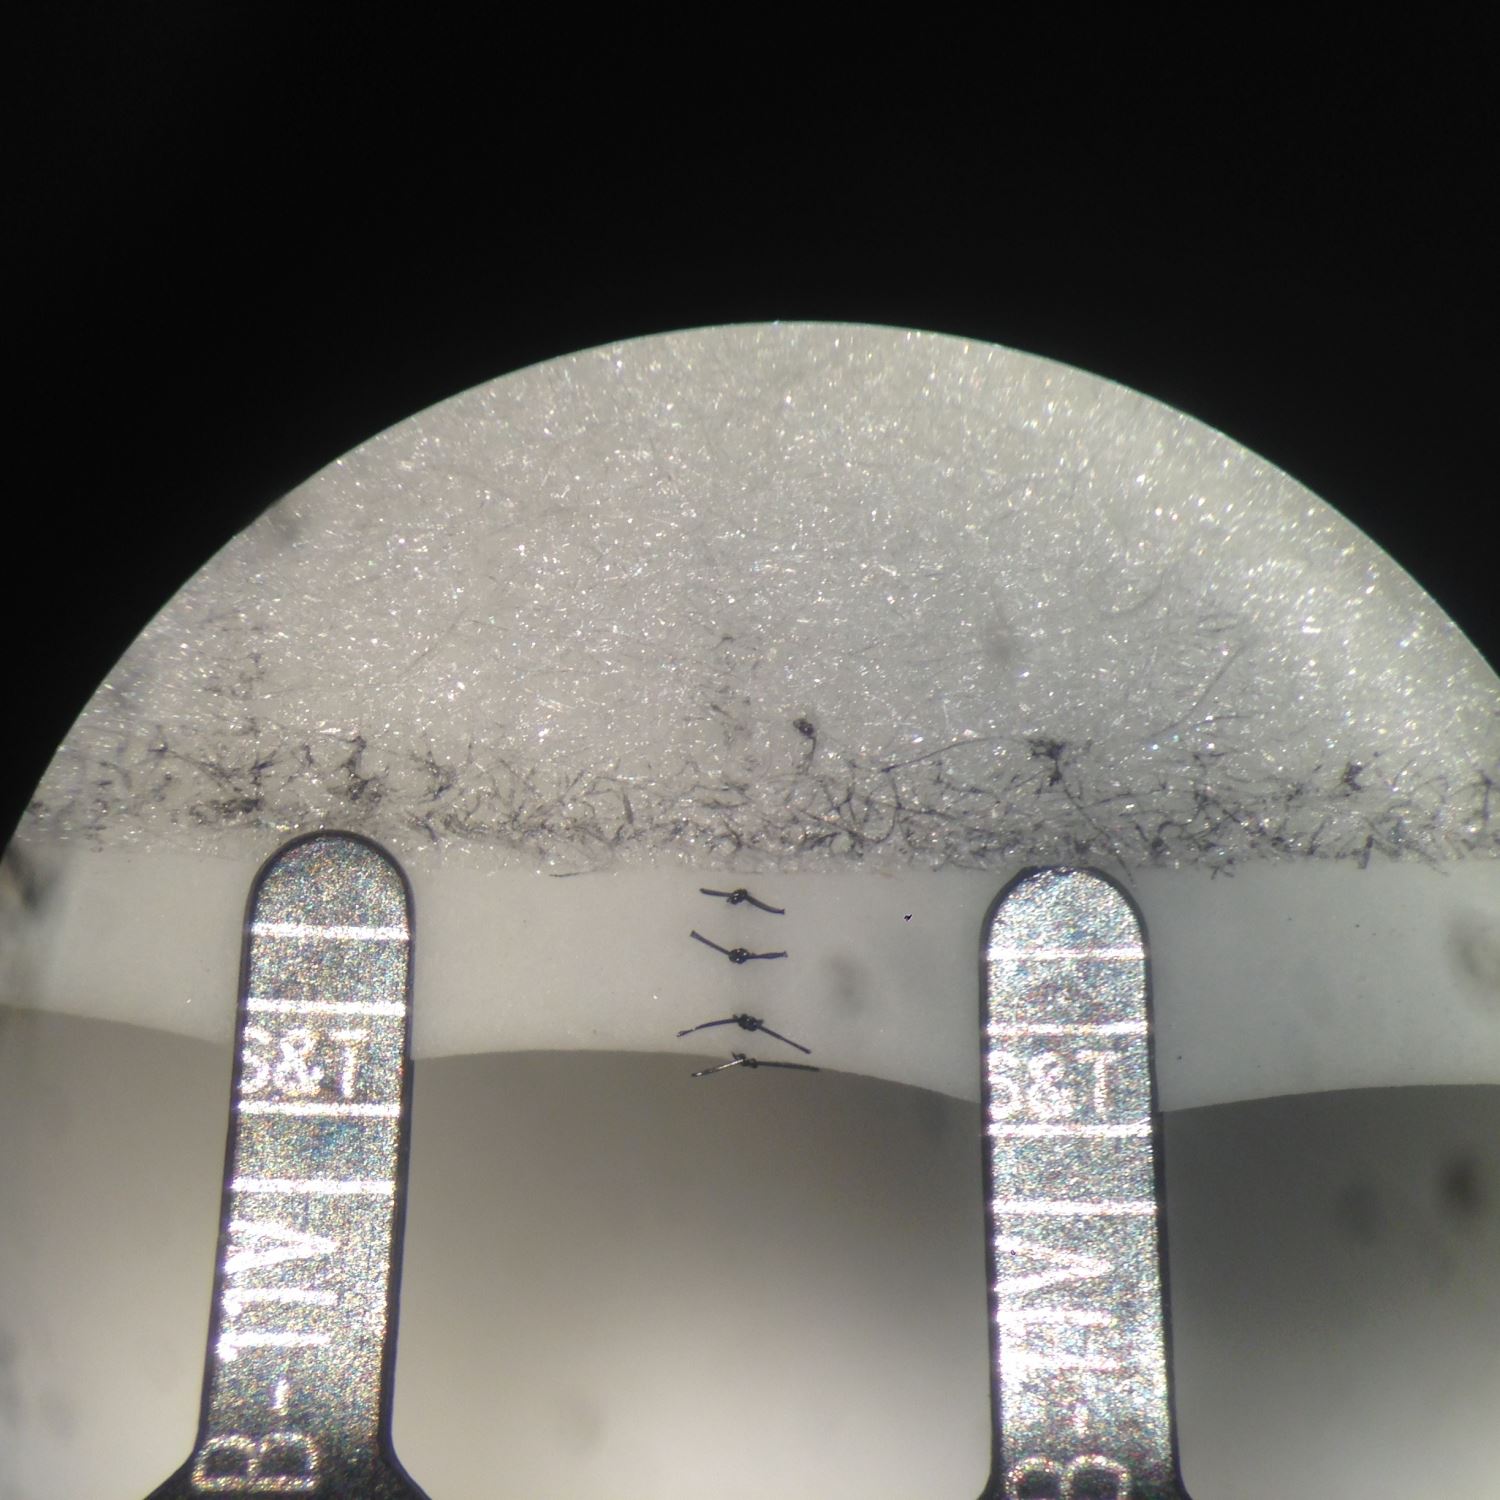

Sutured microanastomosis geometry demonstrating even distribution of Microanastomosis In this text we will briefly discuss the history of microvascular surgery, review current literature on simulation models with the emphasis. We used fresh chicken wings and a microanastomosis technique to create different models according to the vascular pathological. Microsurgery in patients with advanced atherosclerosis is challenging. At the 2009 workshop, we introduced three microanastomosis training models, namely, the synthetic. Microanastomosis.